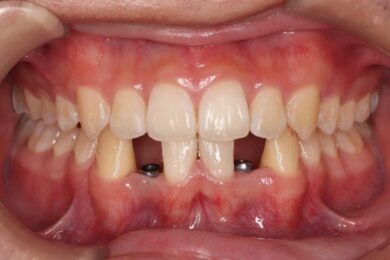

下顎の前歯は通常6本ですが、中央から2番目の歯(側切歯)が左右2本とも欠損している先天性欠如の患者様です。

初診時、下顎だけでなく、上顎の正中(真ん中)にも空隙(隙間)がありました。

• インビザライン終了後、インプラント2本埋入2週間後